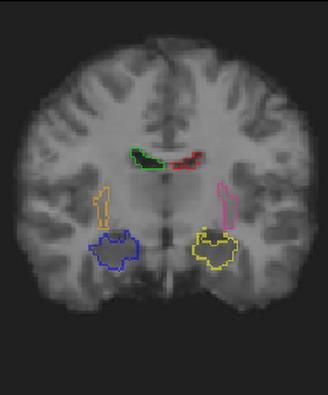

Medical image registration is a fundamental and critical task in medical image analysis. With the rapid development of deep learning, convolutional neural networks (CNN) have dominated the medical image registration field. Due to the disadvantage of the local receptive field of CNN, some recent registration methods have focused on using transformers for non-local registration. However, the standard Transformer has a vast number of parameters and high computational complexity, which causes Transformer can only be applied at the bottom of the registration models. As a result, only coarse information is available at the lowest resolution, limiting the contribution of Transformer in their models. To address these challenges, we propose a convolution-based efficient multi-head self-attention (CEMSA) block, which reduces the parameters of the traditional Transformer and captures local spatial context information for reducing semantic ambiguity in the attention mechanism. Based on the proposed CEMSA, we present a novel Symmetric Transformer-based model (SymTrans). SymTrans employs the Transformer blocks in the encoder and the decoder respectively to model the long-range spatial cross-image relevance. We apply SymTrans to the displacement field and diffeomorphic registration. Experimental results show that our proposed method achieves state-of-the-art performance in image registration. Our code is publicly available at \url{https://github.com/MingR-Ma/SymTrans}.